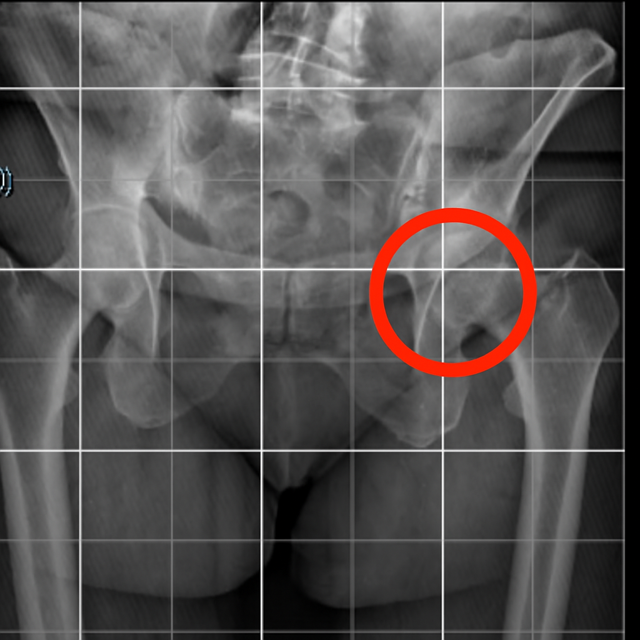

En muchos dolores de talón, el origen está más arriba, en la cadera.

La cadera: el motor silencioso de la marcha.

La cadera no solo nos permite caminar o correr; es la bisagra que dirige la fuerza desde el tronco hacia la pierna.

Cuando esa bisagra pierde movilidad, el cuerpo se ve obligado a compensar.

Esas compensaciones, aunque imperceptibles al principio, alteran el patrón de carga que llega al pie y terminan castigando al talón.

Una limitación en la rotación interna o externa de cadera provoca que la pierna tienda a compensar este déficit al caminar o correr.